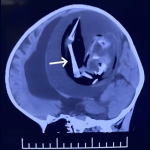

Médicos encontram feto com braços dentro do crânio de bebê de 1 ano

Feto de 18 centímetros de irmão gêmeo de menina tinha ficado armazenado dentro do crânio da bebê, que não sobreviveu à cirurgia